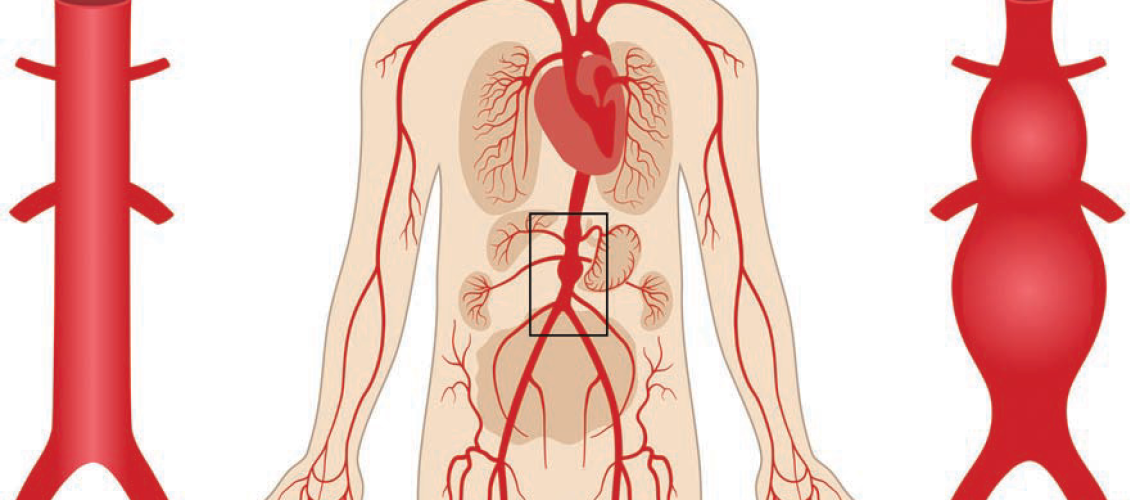

آئورت، بزرگترین شریان بدن انسان، نقش بسیار مهمی در انتقال خون غنی از اکسیژن از قلب به سایر قسمتهای بدن ایفا میکند. پاره شدن آئورت یا “آنوریسم آئورت” یک وضعیت اورژانسی پزشکی بسیار جدی است که میتواند به سرعت به مرگ منجر شود. این وضعیت نیازمند تشخیص و درمان فوری است و عدم توجه به موقع میتواند عواقب جبرانناپذیری به همراه داشته باشد. در این مقاله، به بررسی جامع علائم، دلایل، و روشهای درمان پاره شدن آئورت پرداخته و در ادامه بهترین پزشکان متخصص قلب و عروق اصفهان برای درمان این مشکل معرفی میشوند.

آئورت به عنوان بزرگترین شریان بدن از بطن چپ قلب خارج میشود و از طریق شاخههای مختلف خود، خون اکسیژندار را به تمام اعضای بدن میرساند. این شریان از دو بخش اصلی تشکیل شده است: آئورت صعودی و آئورت نزولی. همچنین آئورت در ناحیه قفسه سینه به سه قسمت تقسیم میشود: آئورت قوسی، آئورت سینهای و آئورت شکمی.

- آنوریسم آئورت: تورم یا گشاد شدن غیرطبیعی آئورت به دلیل ضعف دیوارههای آن میتواند به پارگی منجر شود.